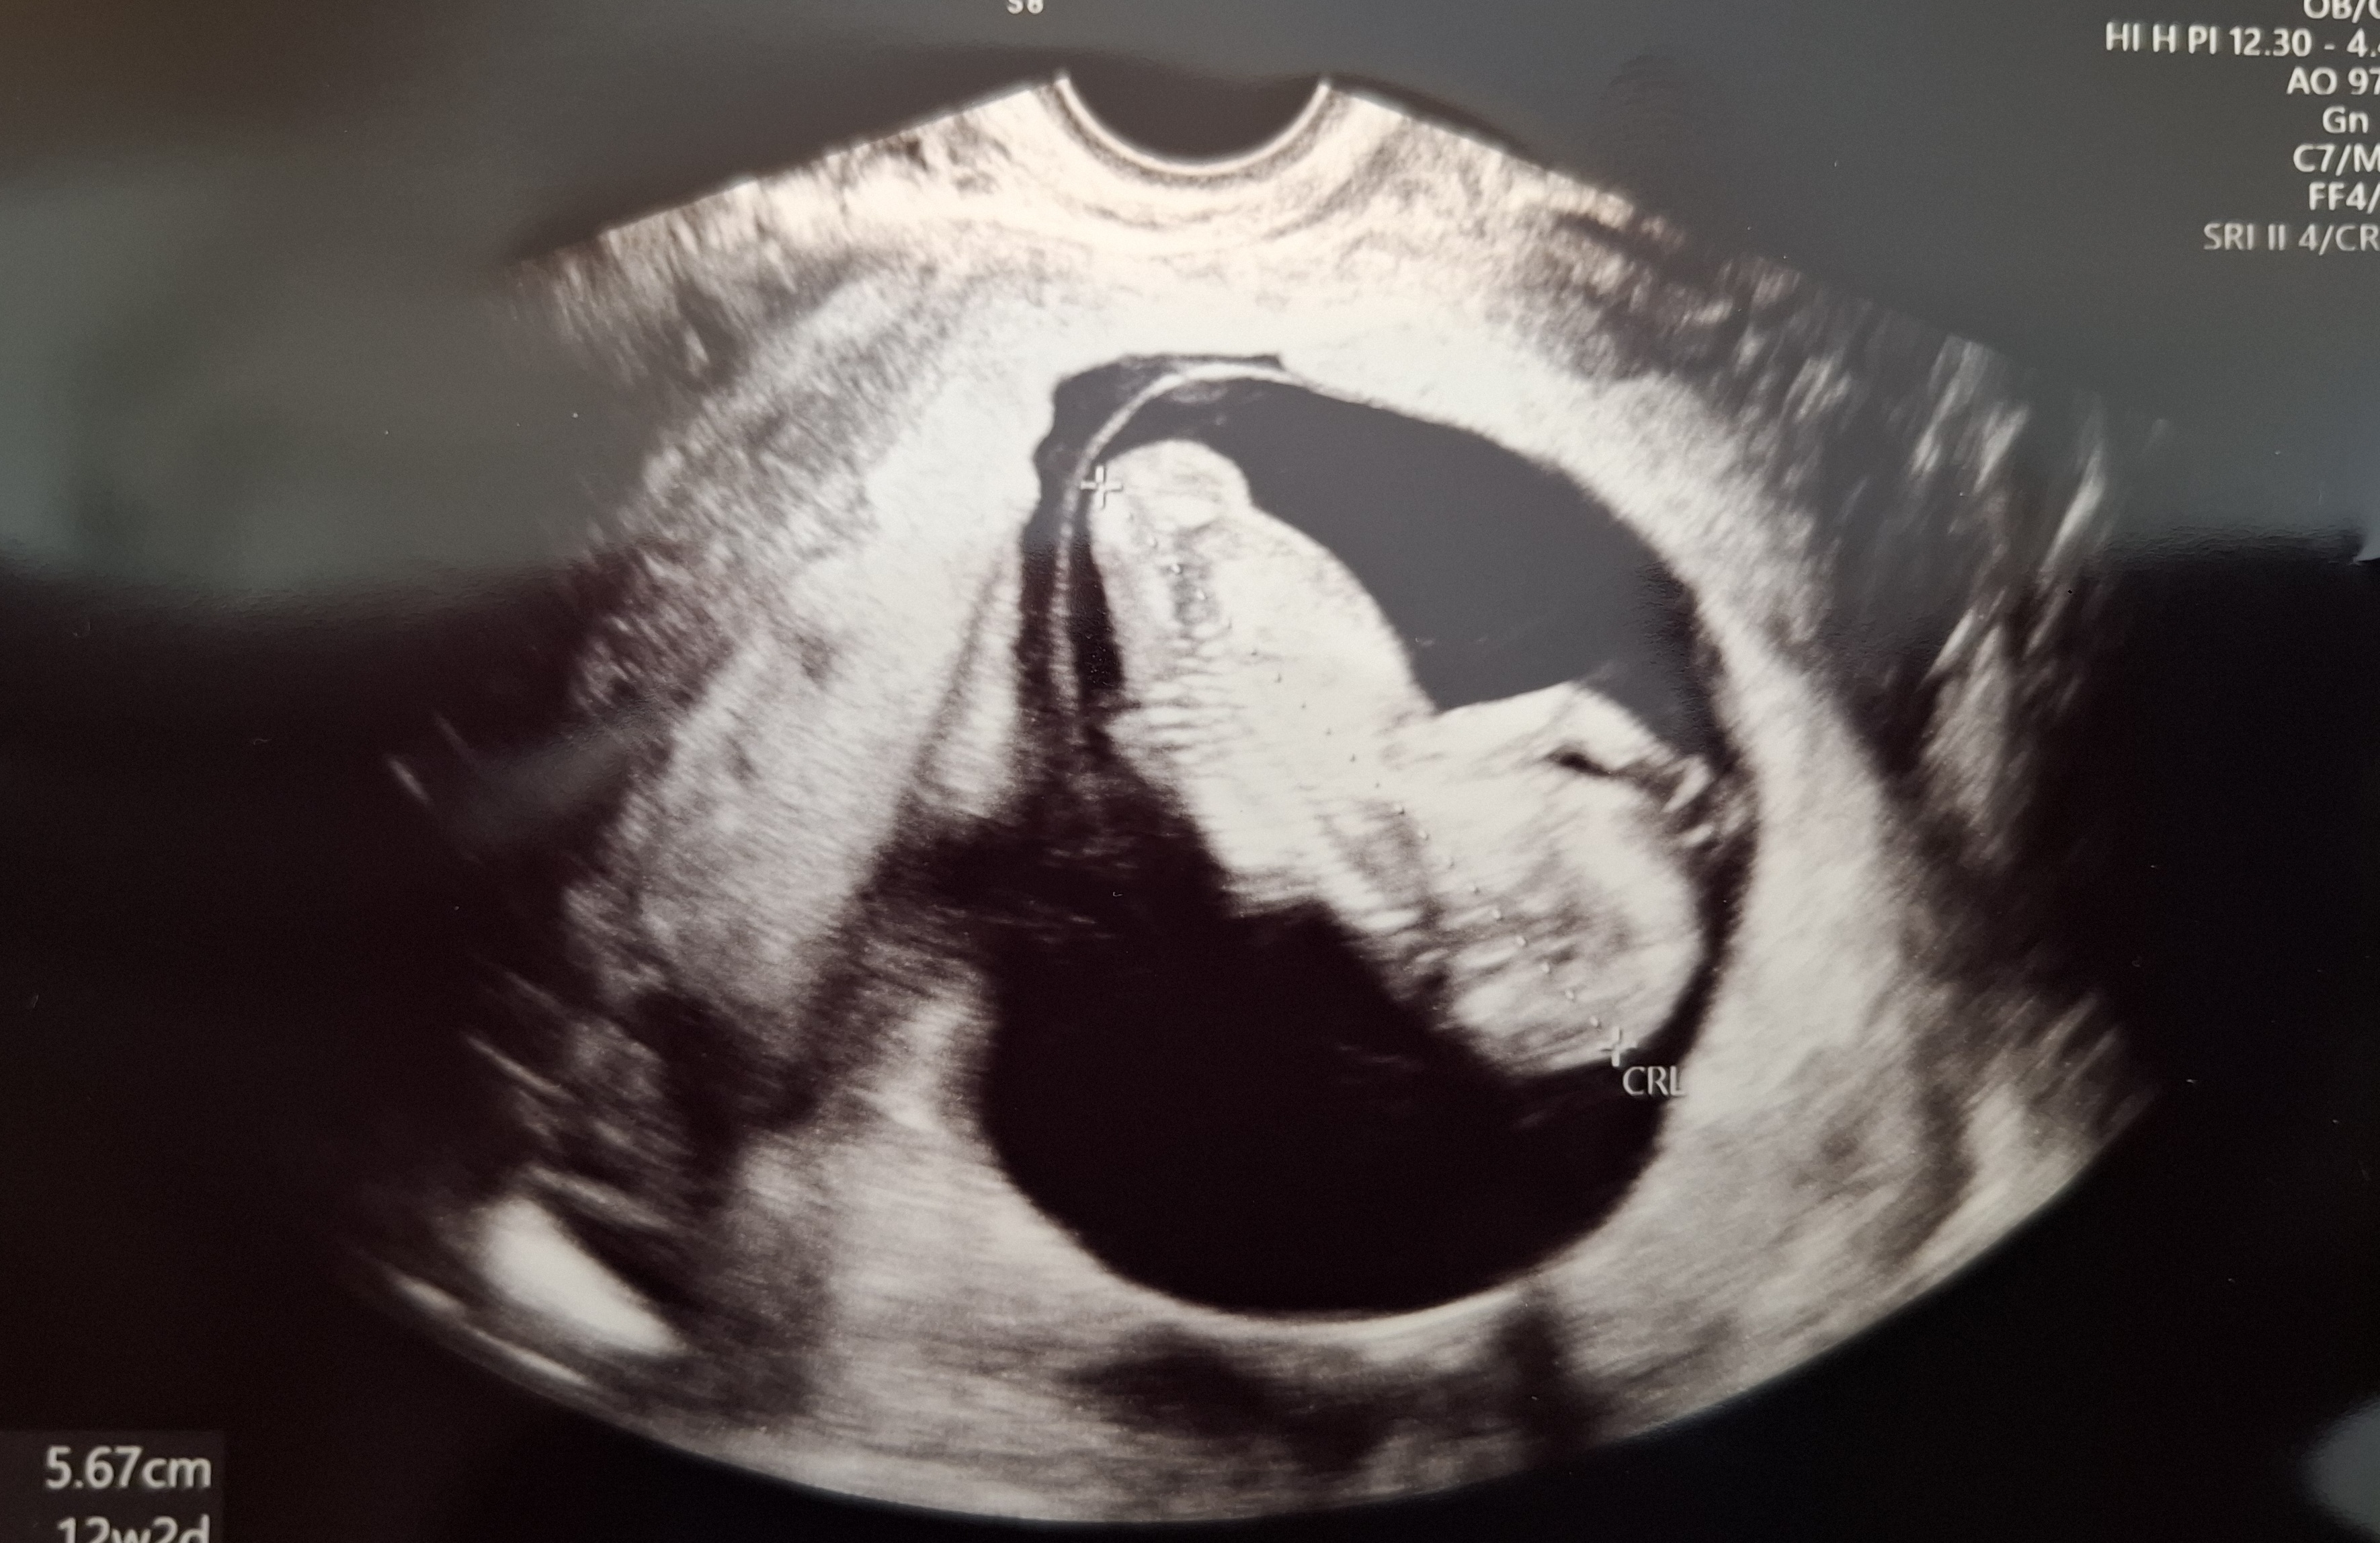

| 가슴 떨리는 임신 이야기를 공유해 주세요. | 병원에 내원하는 동안 걱정스러운 순간도 있었지만, 동시에 마음이 놓이는 순간들도 많았습니다. 특히 임신 확인을 받았을 때, 늘 친절하고 따뜻한 마음으로 대해주신 이유정 원장님을 비롯한 의료진분들께 깊은 감사의 마음이 들었습니다. |

| 치료 도중 느꼈던 가장 기뻤던 순간과 절망적인 것들은 무엇인가요? 잊지 못할 경험이 있나요? | 타 병원에서 두 번의 유산을 겪은 이후라 이번 임신 확인 이후에도 마음이 가볍지만은 않았습니다. 그럼에도 불안할 때마다 차분하게 이끌어 주시고, 궁금한 점들을 충분히 설명 듣고 좋은 진료 결과를 확인했을 때 안도와 기쁨이 함께 찾아왔습니다. 그래서인지 서울아이비에프와 함께 한 치료 과정에서 크게 절망하거나 좌절감을 느꼈던 순간은 없었습니다. |